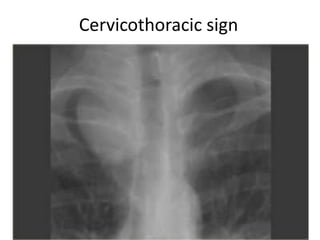

Cervicothoracic sign

Well defined mass seen above the clavicle is

Cervicothoracic sign Well definedmass seen above the clavicle is always situated in posterior compartment ,the anterior compartment mass being in contact with soft tissue rather than aerated lung is ill defined